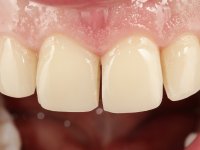

Paciente do sexo masculino, com 36 anos, não fumador. Fez tratamento ortodôntico e reabilitou esteticamente o sector anterior com restaurações em resina composta. As restaurações apresentavam um aumento vertical médio de 2 mm em relação o bordo incisal. Apresentavam-se esteticamente satisfatórias, mas com algumas fraturas incisais. O dente 1.5 apresentava um processo apical e o dente 2.6 apresentava tratamento endodôntico e uma lesão endo-periodontal. No maxilar inferior no local do dente 3.5 apresentava um implante com uma coroa aparafusada e o dente 8.5 ainda estava presente em boca com agenesia do dente 4.5. O paciente apresentava uma ligeira perda da dimensão vertical da oclusão provavelmente associada a um visível desgaste das superfícies oclusais. O periodonto era espesso e apresentava uma excelente higiene oral.

Após análise clínica e imagiológica foi proposto ao paciente recuperar a dimensão vertical da oclusão essencialmente à custa de incrementos oclusais inferiores utilizando “overlays” no sector posterior e facetas no sector anterior. A coroa aparafusada sobre o implante 3.5 seria substituída, no sentido de acompanhar este incremento. Na maxila o dente 2.6 teria extração indicada e posteriormente seria reabilitado com um implante e respetiva coroa. No sentido de reabilitar esteticamente o paciente duma forma minimamente invasiva, foi proposta a colocação de facetas feldespáticas no sector antero-superior. O objetivo de aumentar ligeiramente a D.V.O., teria como função “proteger” eficazmente o sector antero-superior.

Realizado o diagnóstico e tomada a decisão quanto ao tratamento a executar, tornou-se importante definir qual a sequência de trabalho a adotar no sentido de conseguir a reabilitação da D.V.O. (V.D.O), de forma progressiva e equilibrada. Na primeira fase fez-se uma pré-impressão da arcada inferior com silicone tipo “putty” e em seguida realizou-se o preparo dentário de todo o sector posterior. O preparo para os overlays foi feito coronalmente à linha amelo cementaria no sentido de ser o mais conservador possível. A impressão foi feita com técnica de dupla mistura após afastamento gengival realizado com pasta de caulino. A provisória foi realizada com resina composta de polimerização dual. Em laboratório foram realizados os overlays após se ter aberto ligeiramente (1,5mm) a D.V.O. nos modelos montados em articulador semi-ajustável. Simultaneamente o sector antero-inferior foi encerado no sentido de acompanhar este aumento da D.V.O. Também foi confecionada uma chave de silicone translucido para posterior confeção dos provisórios antero-inferiores. Em boca foi primeiro realizada a provisionalização dos dentes anteriores utilizando resina composta previamente aquecida após preparação das superfícies dentárias para a adesão. Foi colocado o dique de borracha para promover o isolamento absoluto e posteriormente foram colados os overlays. Em laboratório foi realizada nova chave de silicone para confecionar os provisórios antero-superiores. Seguidamente em boca foram preparados os seis dentes antero-superiores após colocação do fio de afastamento gengival. Feita a preparação adequada das superfícies dentárias foi realizada a impressão com técnica de dupla mistura e a respetiva provisória. Em laboratório foram confecionadas 6 facetas feldespáticas num modelo de trabalho tipo “Geller”. A provisória foi removida e as facetas foram coladas em boca utilizando um isolamento relativo competente. Esta opção foi tomada em virtude de uma prévia experiencia negativa com a colocação do dique de borracha na mandibula. Após a colagem dos laminados antero-superiores foram dadas 12 semanas para avaliar a adaptação do paciente à nova situação e então iniciar a confeção das facetas antero-inferiores. Após colocação do fio de afastamento gengival. foram feitos os preparos dentários adequados e em seguida foi feita a impressão. Também foi feita a preparação do dente 3.4 que, entretanto, tinha sofrido uma fratura do overlay. As facetas e a restauração do 3.4 foram realizadas num modelo de trabalho tipo “Geller”. Após remoção da provisória, as facetas foram coladas em boca, utilizando um isolamento relativo pelas razões apontadas anteriormente. Após colocação do trabalho o paciente foi reabilitado por outros colegas com um implante na zona do 2.6 e substituição da coroa aparafusada sobre o implante colocado no local do 3.5. Posteriormente surgiram fraturas nos overlays dos dentes 4.7 e 3.7 que foram reabilitados com overlays em Zr.